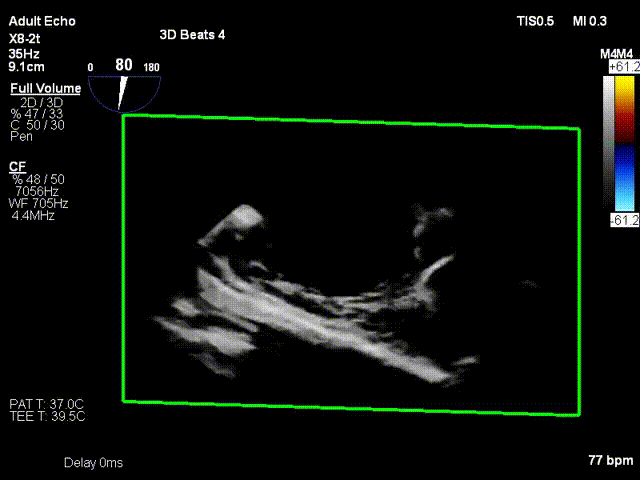

术前与术后30天三尖瓣反流比较